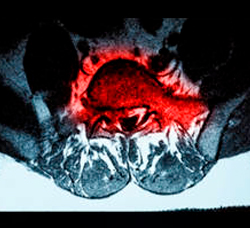

Una hernia discal se produce cuando el contenido del disco intervertebral L5-S1 se sale del disco y se introduce en el canal lumbar, en ocasiones el material discal puede comprimir y afectar a las estructuras nerviosas. cuando tenemos una hernia L5-S1 se pueden afectar la raíz L5 a su salida por el agujero que se forma entre ambas vértebras, y la raíz S1 antes de que salga de la columna. Si la hernia es muy grande también se pueden afectar las raíces sacras y producirse un síndrome de cola de caballo.